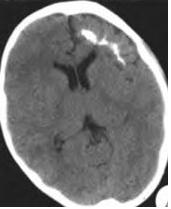

Sturge-Weber综合征

Sturge-Weber综合征是一种以皮肤、脑、眼部损害为临床特征的静脉微血管系统的先天性病变。

临床表现为面部“葡萄酒”色血管瘤、青光眼、癫痫发作、偏瘫及智力下降等。

影像表现为皮质不同程度的钙化、脑萎缩、脑回样脑膜强化及深静脉增多、扩张。